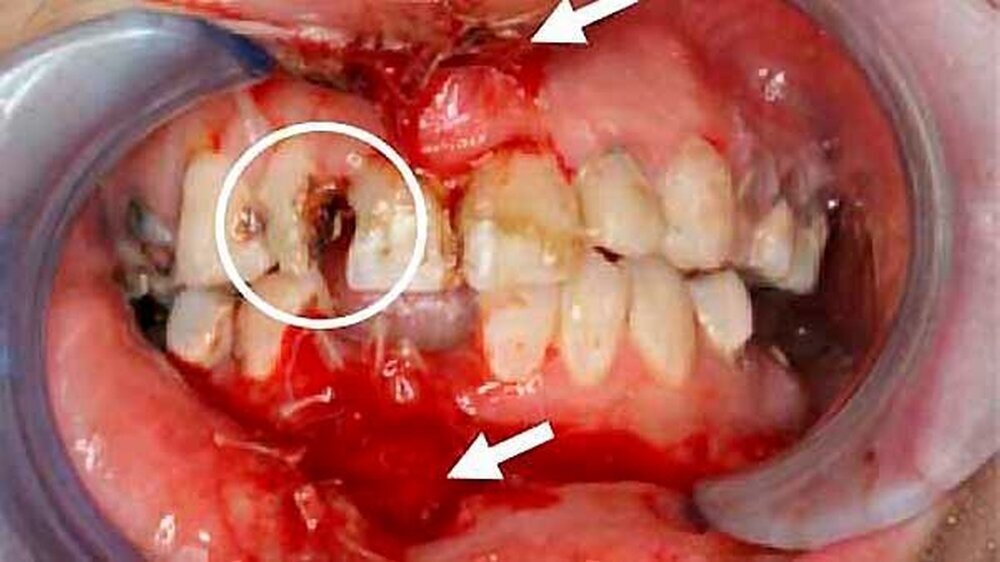

Eine 26-jährige Frau wurde nach einem Fahrradunfall in Begleitung der Polizei in unsere interdisziplinäre Notfallaufnahme mit multiplen und ausgeprägten extra- und intraoralen Weichteilverletzungen sowie einer Alveolarfortsatzfraktur des Ober- und Unterkiefers eingeliefert.

Die weitere klinische Inspektion ergab intraoral den Befund eines kariös tief zerstörten Restzahngebisses mit multiplen, teils gelockerten, nicht erhaltungswürdigen Zähnen.

) erfolgte in Vollnarkose eine Wundrevision und Reposition der Nasenbeinfraktur. Zusätzlich erfolgte - mit Ausnahme der dentes caninii - die operative Entfernung der tief zerstörten und nicht erhaltungswürdigen Restbezahnung des Ober- und Unterkiefers in Kombination mit einer modellierenden Osteotomie sowie einem plastischen, speicheldichten Wundverschluss.